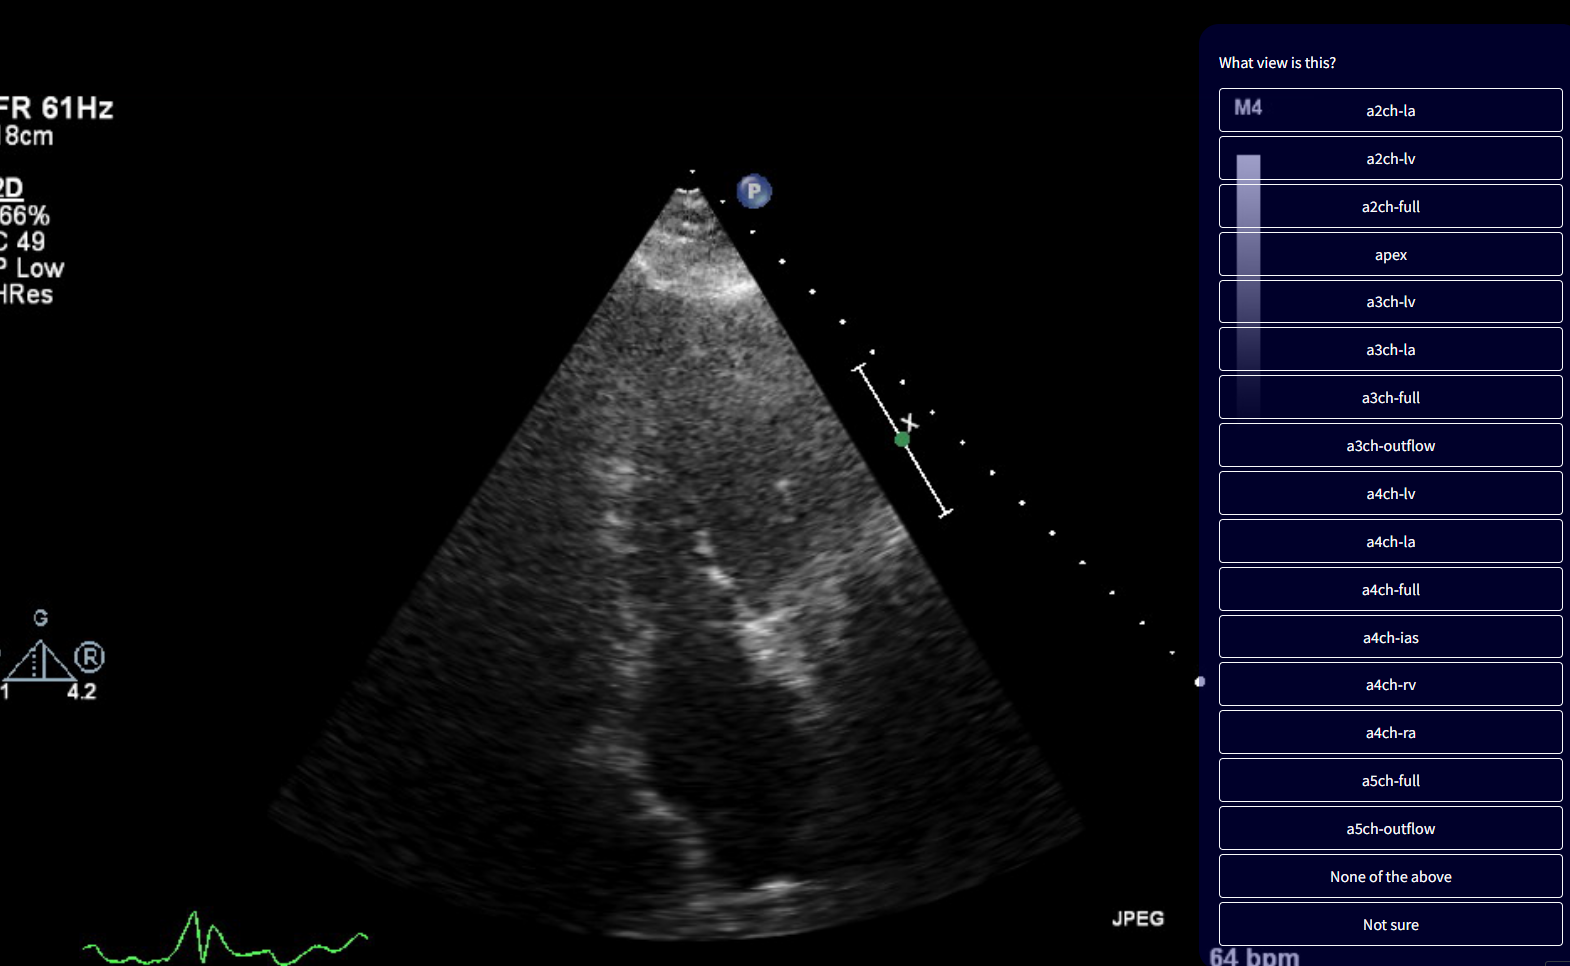

We are training an AI model for detailed classification of echocardiographic views, covering 47 distinct categories.

Due to the large number of views, some challenging cases may arise.

For instance, certain views — such as the apical 3-chamber and apical 4-chamber — can appear similar, making it difficult to determine the correct label.

Please examine each image carefully to distinguish between these views.

If an image does not fit any available category, select “None of the above”.

If it fits a category but you’re unsure which one, select “Not sure”.

a2ch-la Apical 2-chamber, focused on the left atrium

a2ch-lv Apical 2-chamber, focused on the left ventricle

a2ch-full Apical 2-chamber

apex Any apical window, focused on the apex

a3ch-la Apical 3-chamber, focused on the left atrium

a3ch-lv Apical 3-chamber, focused on the left ventricle

a3ch-full Apical 3-chamber

a3ch-outflow Apical 3-chamber, focused on the aortic valve

a4ch-la Apical 4-chamber, focused on the left atrium

a4ch-lv Apical 4-chamber, focused on the left ventricle

a4ch-full Apical 4-chamber

a4ch-ias Apical 4-chamber, focused on the inter-atrial septum

a4ch-ra Apical 4-chamber, focused on the right atrium

a4ch-rv Apical 4-chamber, focused on the right ventricle

a5ch-full Apical 5-chamber

a5ch-outflow Apical 5-chamber, focused on the aortic valve